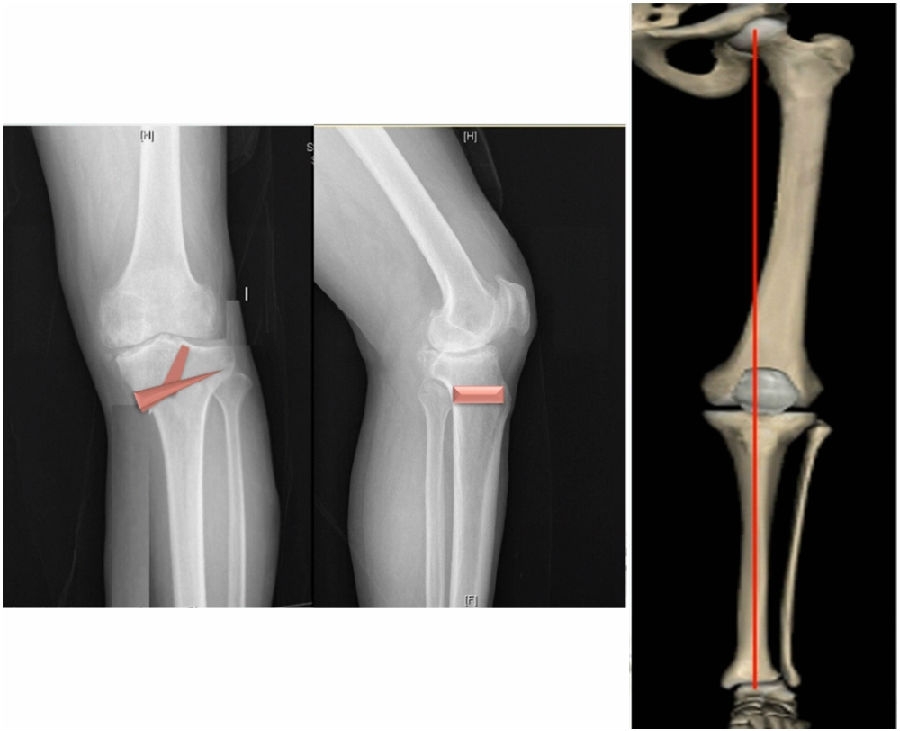

术中先打克氏针确定截骨方向,先做关节内截骨,截完后测量下肢力线,发现并没达到术前设计的Fujisawa点。

术中影像资料

随后用骨刀继续向前敲,做HTO内侧开放楔,截骨完成后内侧固定,并测量下肢力线,此时达到术前设计的要求。

该患者撑开较大,取了髂骨进行植骨。

髂骨植骨

最终力线

术后检查证实达到了术前预期的手术效果,关节线达到了平行,半脱位得到矫正,同时关节线和地面水平。病人行走达到了理想的效果。

术后X线

患者术后4个月截骨愈合,膝关节稳定维持得非常好。

术后4个月